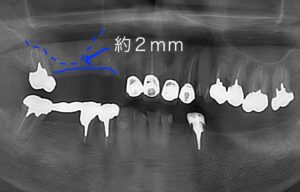

レントゲンでは上の点線が副鼻腔、下の線が

骨のラインで約2mmしか骨がありません。

インプラントに初期固定が得られましたので

同時法で行いました。

その後、さらにその奥もサイナスリフトを行いました。

青丸が骨に穴をあけた部分です。